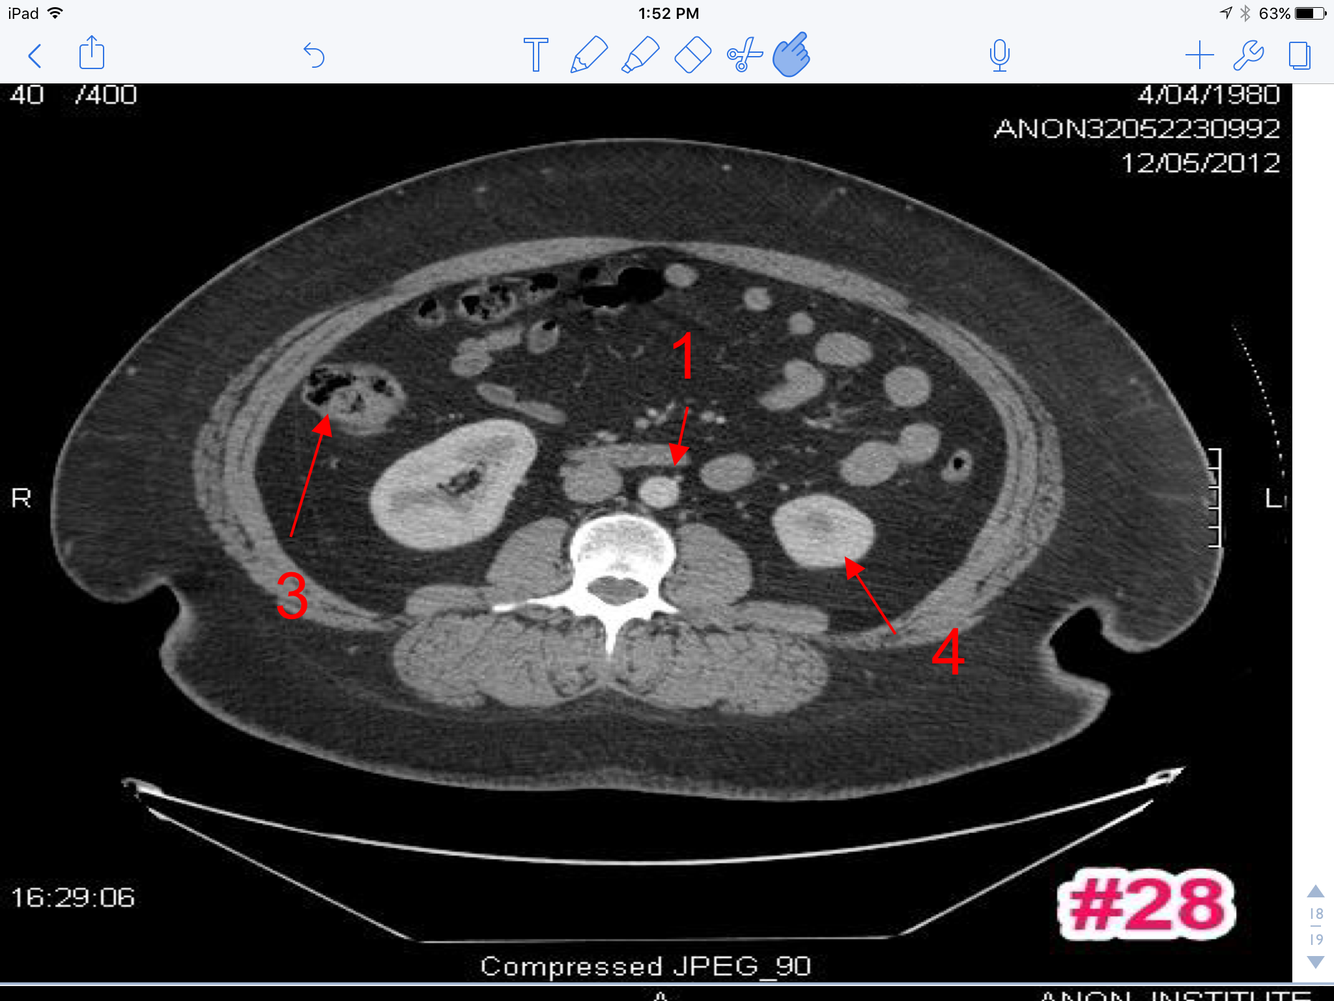

15

A

1. Transverse colon

2. Ascending colon

3. Loops of small bowel

4. Rt. renal V

5. Superior mesenteric A

6. Superior mesenteric V

7. Psoas major M

16

3. Rt renal pelvis